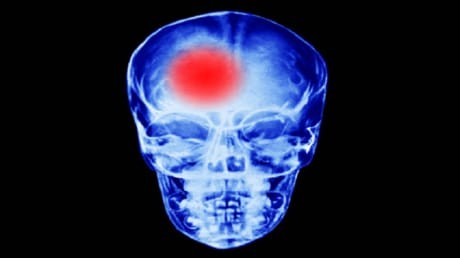

أسباب الجلطة الدماغية في مرحلة الشباب ... تعرف عليها

كشف الدكتور يوري سيريبريانسكي، أخصائي أمراض القلب، أسباب حدوث الجلطة الدماغية في مرحلة الشباب.

ويشير الأخصائي في حديث إلى صحيفة "فيتشيرنايا موسكفا"، إلى أن الجلطة الدماغية في مرحلة الشباب يمكن أن تحدث نتيجة "الاستعداد الوراثي، أو ارتفاع مستوى الكوليتسرول، أو نتيجة ارتفاع مستوى ضغط الدم، أو مرض السكري".

وينصح الأخصائي الأشخاص الذين لديهم في العائلة أشخاص أصيبوا بهذه الأمراض، مثل ارتفاع مستوى الكوليسترول في الدم، بالخضوع للعلاج مدى الحياة. كما يمكن أن الإجهاد والعواصف المغناطيسية بمثابة محفز لحدوث الجلطة الدماغية.

ووفقا له، لا تؤدي الجلطة الدماغية المبكرة إلى الموت المبكر. ولا تؤثر في متوسط عمر الإنسان. ولكن هذا يتوقف على نوع الجلطة الدماغية وعواقبها. ويمكن منع حدوثها عن طريق إجراء الفحوصات اللازمة بصورة دورية ومنتظمة.